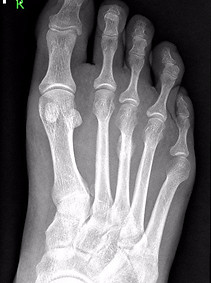

Rentgenový snímek v prvních dnech po rozvoji bolestí nezobrazuje zlomeninu, anebo poškození tkáně. Změna na RTG se projeví až s odstupem několika týdnů (2 až 3 týdny). V místě postižení se s odstupem vytváří nová kostní tkáň a na RTG snímku je nártní kost jakoby obalena shlukem nové kosti (kostní svalek). Postižení nártní kosti je většinou v místě přechodu těla v hlavici. Snímky můžou také diagnostikovat nepoměry mezi nártními kostmi (primární metatarsalgie), anebo změny na prvním metatarsofalangovém skloubení, které jsou typické pro sekundární metatarsalgie.